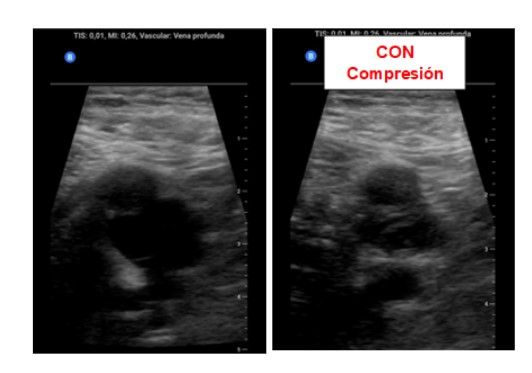

Ante la sospecha de Trombosis venosa profunda realizamos ecografía de compresión venosa de miembros inferiores detectando la falta de colapsabilidad de la femoral común y femoral superficial del miembro inferior derecho, cosa que no pasaba en el izquierdo.